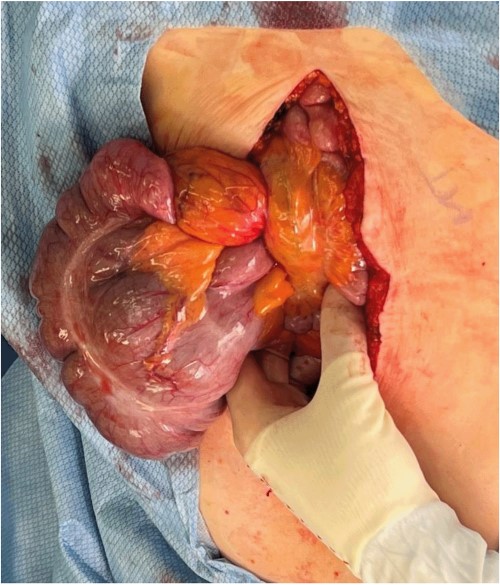

A midline laparotomy was made. A midgut volvulus was encountered immediately upon entering the abdomen and was subsequently reduced from the left upper quadrant. The cecal and ascending colon volvulus had a 540 degree rotation with viable tissues on reduction; however, the ascending colon had a narrow, non-adherent mesentery allowing a point of volvulus while also folding over a Ladd’s band attached to the right lower quadrant of the abdomen. The bowel was then run, and it was confirmed that there was no present ligament of Treitz and that the patient did indeed have congenital malrotation (Fig. 2). There was no retroperitoneal component of duodenum, and it was completely without fixation to other structures. Ladd’s bands were encountered and lysed (Fig. 3).

Evisceration of the midgut volvulus upon entry into the abdomen.

Identification of Ladd’s bands and lack of retroperitoneal course of the duodenum after detorsion of the midgut volvulus.